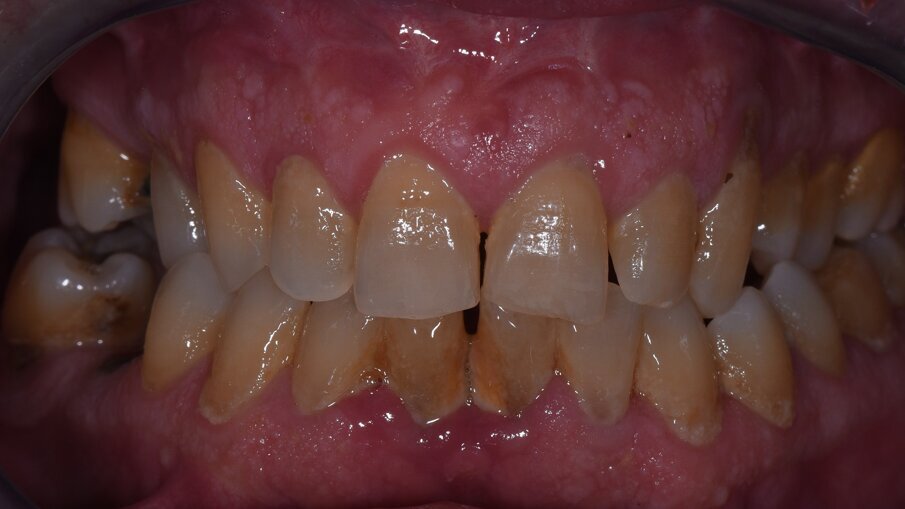

Vengono rilevati gli indici clinici e vengono condivise con il paziente le immagini raccolte con la videocamera intraorale, così da motivarlo di fronte alla presenza di tartaro e infiammazione gengivale e mostrargli le aree critiche. Viene apposto il rilevatore di placca alla fluorescina ed illuminato da una lampada fotopolimeralizzante, che permette di visualizzare la topografia del biofilm batterico (D-BIOTEK-TECNICHE)2, in modo da condividere con il paziente i siti più a rischio del cavo orale (Figg. 1a-2f).